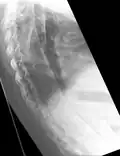

Lateral X-ray of the mid back in ankylosing spondylitis -

The earliest changes demonstrable by plain X-ray shows erosions and sclerosis in sacroiliac joints. Progression of the erosions leads to widening of the joint space and bony sclerosis. X-ray spine can reveal squaring of vertebrae with bony spur formation called syndesmophyte. This causes the bamboo spine appearance. A drawback of X-ray diagnosis is the signs and symptoms of AS have usually been established as long as 7–10 years prior to X-ray-evident changes occurring on a plain film X-ray, which means a delay of as long as 10 years before adequate therapies can be introduced.[25]